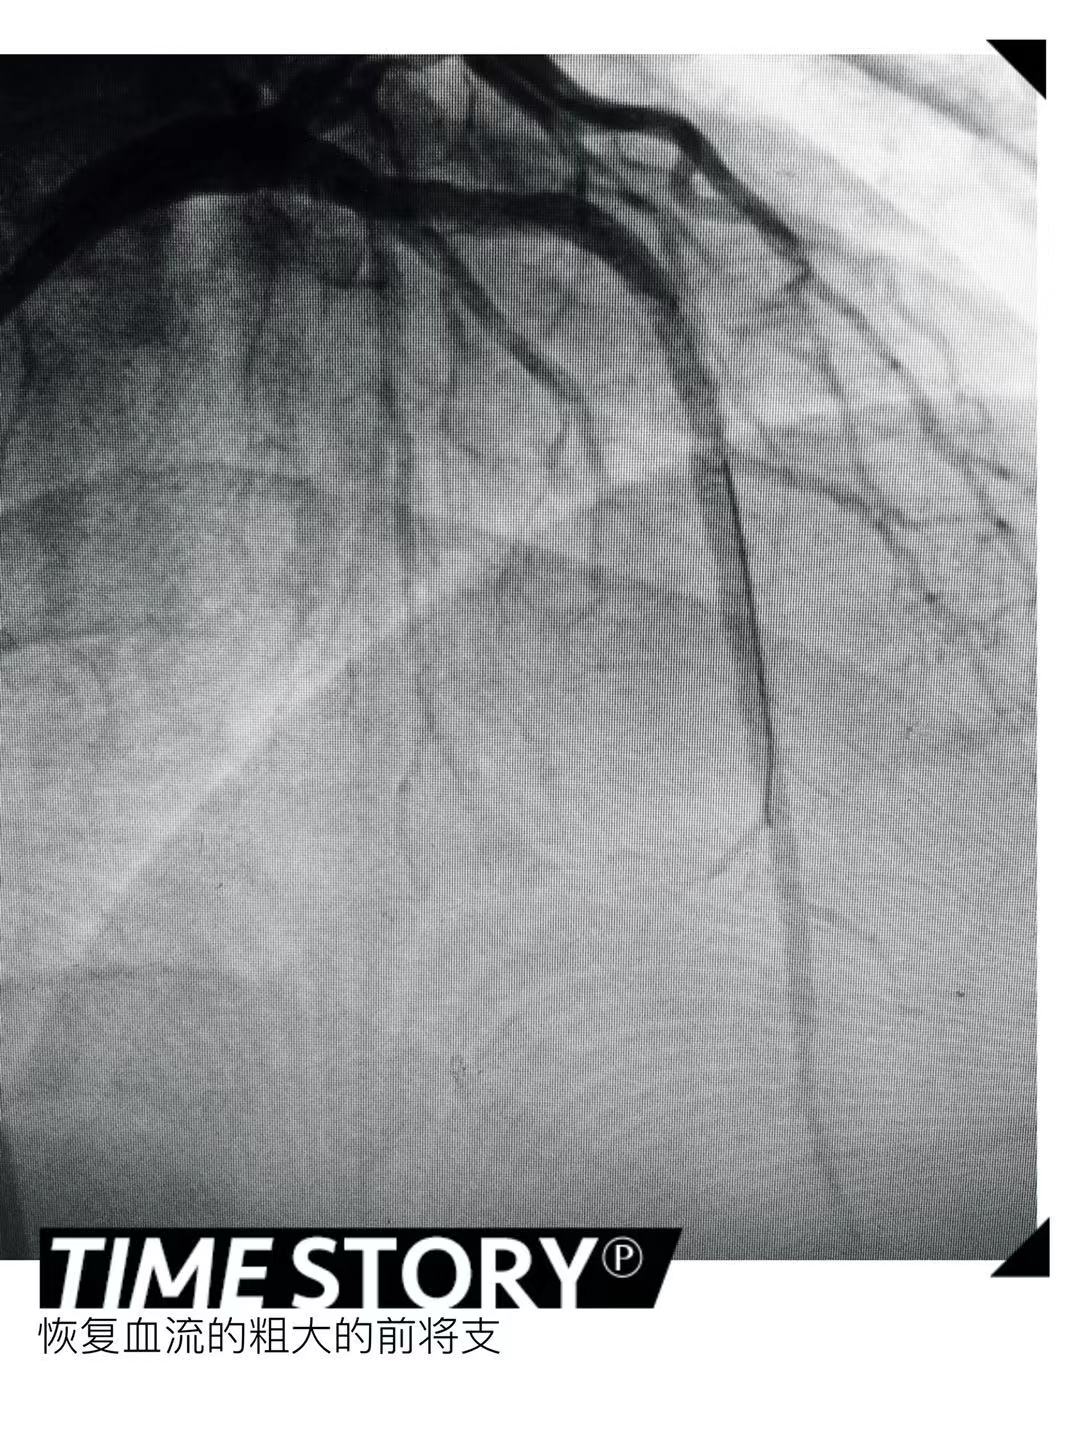

经过充分的术前准备,2019年10月23日由赵朝主任、陆艳副主任进行冠状动脉造影检查,结果显示冠状动脉严重三支病变,左前降支近段100%闭塞,间隔支向左前降支远段形成侧支循环;回旋支中段100%闭塞,右冠状动脉全程瘤样扩张,远端95%以上狭窄,右向左侧支循环很差(逆向技术使用概率很小)。决定先处理最重要的左前降支。正向技术尝试半小时左右失败,由于CTO闭塞残端开口不清、且自认为有较好的同侧间隔支逆向,转换为同侧逆向技术,由于近远端交通的间隔支血管过度迂曲,导丝尝试3个小时左右均不能到达前降支远段。不认输的我们再次转变术式,在血管内超声的指导下,超滑加硬导丝正向刺破闭塞处纤维帽,及时导丝降级,然而导丝不幸进入血管夹层,双腔微导管、手工ADR反复尝试不能回到远段血管真腔,造影剂已经接近300mL,看来只剩下ADR技术。ADR技术是通过输送stingray球囊到良好着陆区的血管夹层内,通过两个相反方向的标识,使硬导丝重回血管真腔的操作。严格按照流程,多次不懈的尝试,功夫不负有心人,导丝回到了前降支远段血管真腔,接下来就是常规操作,手术圆满成功,整个手术历时超过6小时。